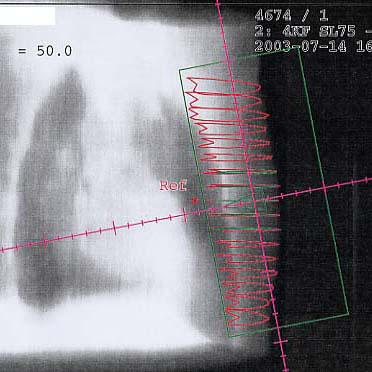

Mammakarzinom: Bestrahlungsplan

Einführung aktuelle Bilder - Einführung Bestrahlungspläne - Einführung Demonstration